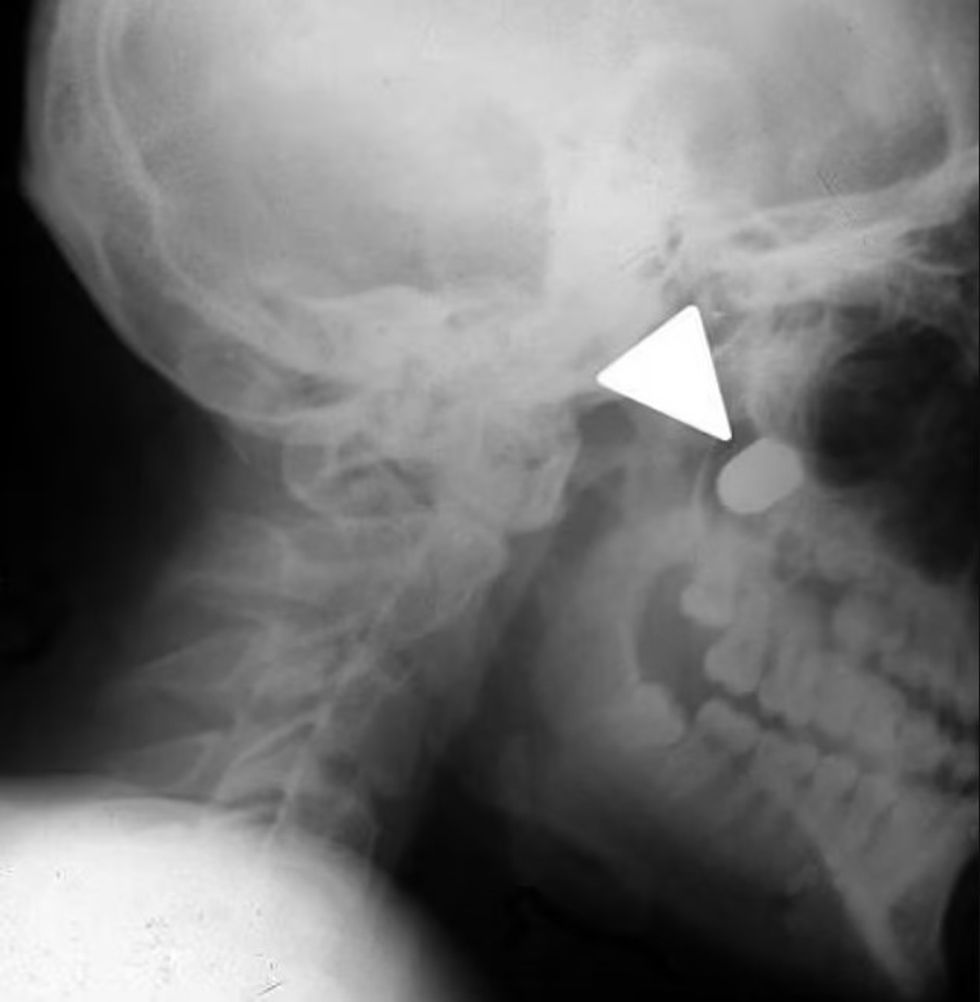

E ky tentim ekzekutim, bëri që plumbi i kalibrit 9 milimetra të depërtojë në qafën e tij, të prek boshtin kurrizor dhe të del përmes nofullës.

Fytyra e djalit ishte shpërfytyruar, kryesisht ana e majtë dhe qafa i ishte ënjtur dhe nuk mund të hapte plotësisht gojën apo të lëvizte kraharorin e majtë, kjo për shkak të lëndimit në boshtin kurrizor.

E gjykuar nga plaga 6 milimetërshe e plumbit, mjekët vlerësuan se ai ishte qëlluar nga një distancë prej 15 centimetra me revolen Makarov. /Telegrafi/